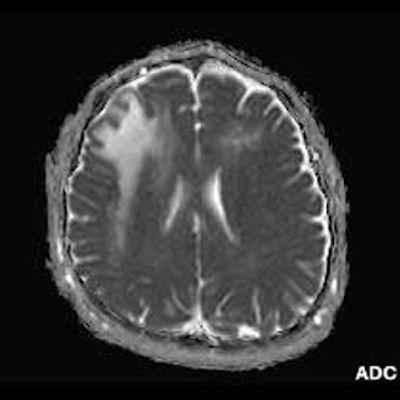

2. B) Aksiyel diffüzyon ağırlıklı serilerde bilateral sağda belirgin frontoparietal subkortikal ve derin periventriküler beyaz cevherde periferal DAG hiperintens ADC hipointens, hafif diffüzyon kısıtlaması (oklar) eşlik etmektedir. IVKM sonrası kesitlerde tarifli alanlarda belirgin kontrast tutulumu (oklar) izlenmedi.